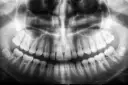

Zdrowe dziecko ma 20 zębów mlecznych, które są kluczowe dla jego rozwoju. W uzębieniu mlecznym znajduje się 10 zębów w szczęce górnej i 10 w szczęce dolnej. Te zęby pełnią ważną rolę w procesie jedzenia oraz w rozwoju mowy. Co istotne, w uzębieniu mlecznym nie ma zębów przedtrzonowych, co odróżnia je od zębów stałych, które pojawiają się później. Zrozumienie, ile zębów mlecznych ma dziecko, jest istotne dla każdego rodzica, aby móc odpowiednio wspierać rozwój malucha.

W uzębieniu mlecznym wyróżniamy trzy główne typy zębów: siekacze, kły oraz zęby trzonowe. Siekacze to zęby, które znajdują się z przodu jamy ustnej i są odpowiedzialne za odgryzanie pokarmu. W zdrowym uzębieniu mlecznym znajduje się 8 siekaczy, 4 w górnej szczęce i 4 w dolnej. Ich kształt i funkcja są dostosowane do tego, aby umożliwić dzieciom łatwe i skuteczne żucie pokarmów, co jest niezbędne w ich diecie.

Kolejnym typem są kły, których w uzębieniu mlecznym jest 4, po 2 w każdej szczęce. Kły są bardziej spiczaste i pełnią rolę w rozdrabnianiu pokarmów. Ostatnim typem są zęby trzonowe, których w mlecznym uzębieniu jest 8. Te zęby znajdują się z tyłu jamy ustnej i są odpowiedzialne za miażdżenie i mieleniu pokarmów, co jest kluczowe dla prawidłowego trawienia. Każdy z tych typów zębów pełni istotną funkcję w procesie jedzenia, co podkreśla ich znaczenie w zdrowym rozwoju dziecka.

W uzębieniu mlecznym wyróżniamy trzy główne typy zębów: siekacze, kły oraz zęby trzonowe. Siekacze to zęby, które znajdują się na przedzie jamy ustnej. W zdrowym uzębieniu mlecznym znajduje się 8 siekaczy, po 4 w górnej i dolnej szczęce. Ich główną funkcją jest odgryzanie pokarmu, co jest kluczowe dla dzieci, które uczą się jeść stałe pokarmy. Kły, których jest 4, pełnią rolę w rozdrabnianiu i chwytaniu pokarmów. Znajdują się po bokach siekaczy i mają bardziej spiczasty kształt.

Ostatnim typem są zęby trzonowe, których w uzębieniu mlecznym jest 8, po 4 w każdej szczęce. Zęby te są większe i mają szeroką powierzchnię, co umożliwia efektywne miażdżenie pokarmów. Dzięki zębom trzonowym dzieci mogą skutecznie żuć twardsze jedzenie, co jest niezbędne dla prawidłowego trawienia. Każdy z tych typów zębów odgrywa istotną rolę w procesie jedzenia i zdrowym rozwoju dziecka.

- 8 siekaczy (4 w górnej szczęce, 4 w dolnej)

- 4 kły (2 w górnej szczęce, 2 w dolnej)

- 8 zębów trzonowych (4 w górnej szczęce, 4 w dolnej)